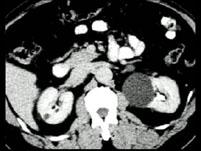

在下列几幅图片均为哪种疾病 ( )A、肾脓肿B、肾脂肪瘤C、肾错构瘤D、肾癌E、肾囊肿

问题 在下列几幅图片均为哪种疾病 ( )

选项 A、肾脓肿 B、肾脂肪瘤 C、肾错构瘤 D、肾癌 E、肾囊肿

答案 E